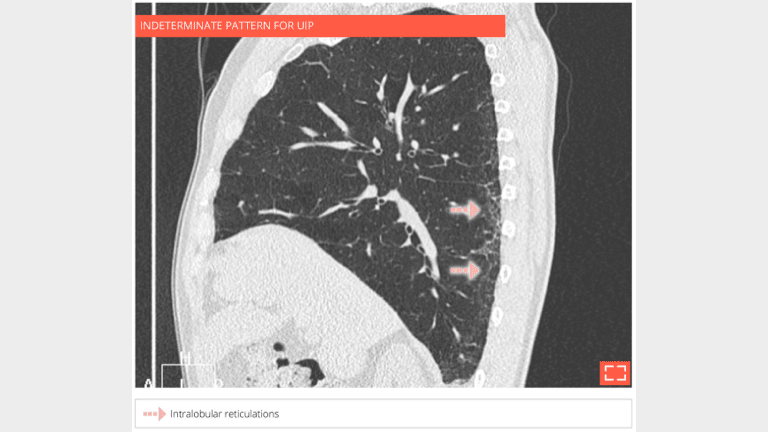

• Isolated and subtle subpleural intralobular reticulations.

• No ground-glass opacity or honeycombing or traction bronchectosis.